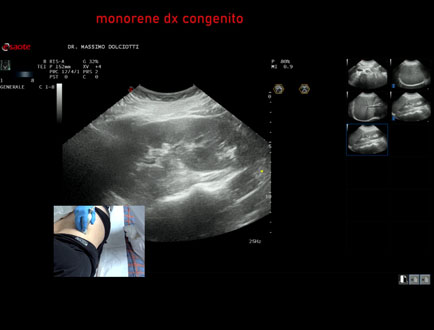

Data inserimento: 03/04/2025

Ecografia del: 26/03/2025

Strumento: Esaote MyLab Eight

Sonda: Convex Multifrequenza 1-8 MHz

Età Paziente: F 51 anni

Motivazione dell'esame: follow up per monorene.

Commento all'esame: le immagini ed il video documentano il rene destro, in sede, di ecostruttura regolare, morfovolumetria superiore alla norma per ipertrofia compensatoria (158 mm diametro longitudinale, 68 mm diametro trasverso, parenchima renale di 23 mm / V.N. > 13 mm), indice di resistenza all'arteria inter lobulare regolare (IR = 0,53 / V.N. < 57).

Conclusioni: monorene destro congenito (congenital right solitary kidney).

Presentazione: Dr. Massimo Dolciotti - Ancona